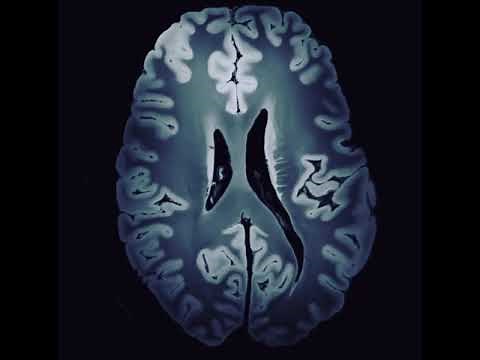

Mayo Clinic 7-Tesla MRI scanner i…

YouTubeMayo Clinic